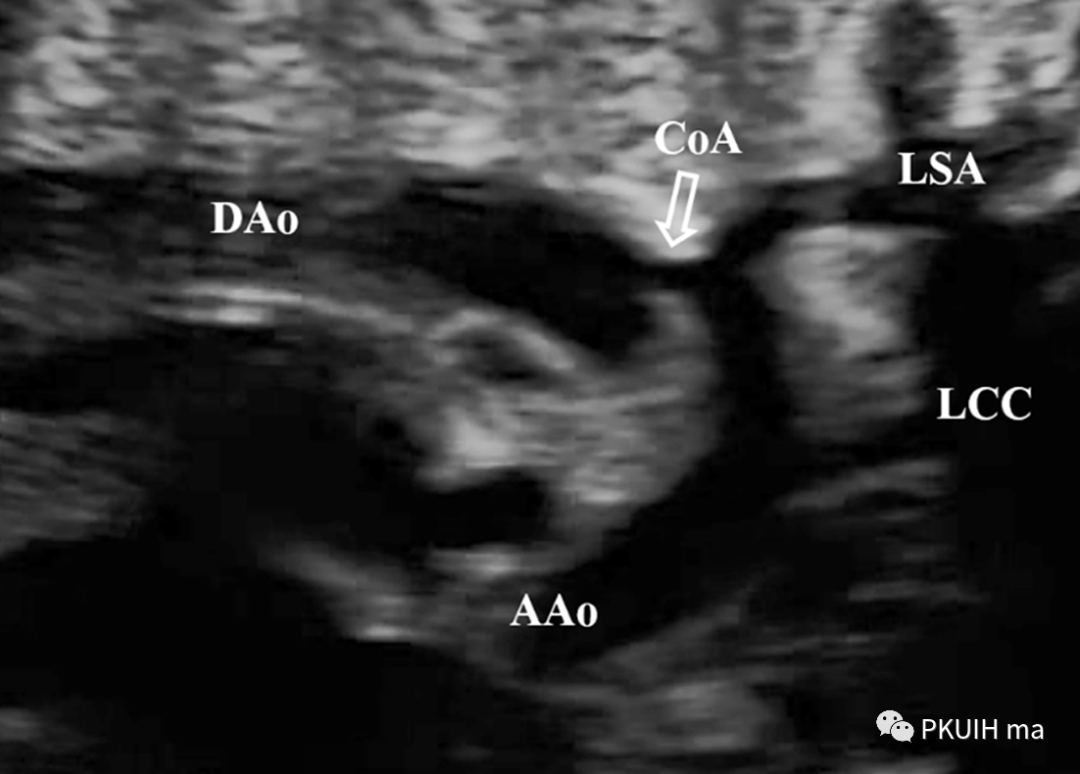

再次可以通过主动脉弓长轴、三血管气管切面观察,主动脉弓长轴切面显示主动脉横弓细窄。主动脉峡部内径与动脉导管内径比值减小与CoA高度相关,峡部与动脉导管内径比≤0.74时发生CoA风险明显增高。同时主动脉弓上的分支血管间距离增大,颈动脉与左锁骨下动脉之间的距离越远,缩窄的可能性就越大。上图CoA主动脉弓长轴切面显示主动脉峡部细窄(AAo:升主动脉,DAo:降主动脉,Ao Arch:主动脉弓,箭头所示为缩窄部位)上图 CoA胎儿三血管气管切面,图像显示主动脉峡部明显细窄,内径1.0 mm (Duct:动脉导管;Isthmus:主动脉峡部)